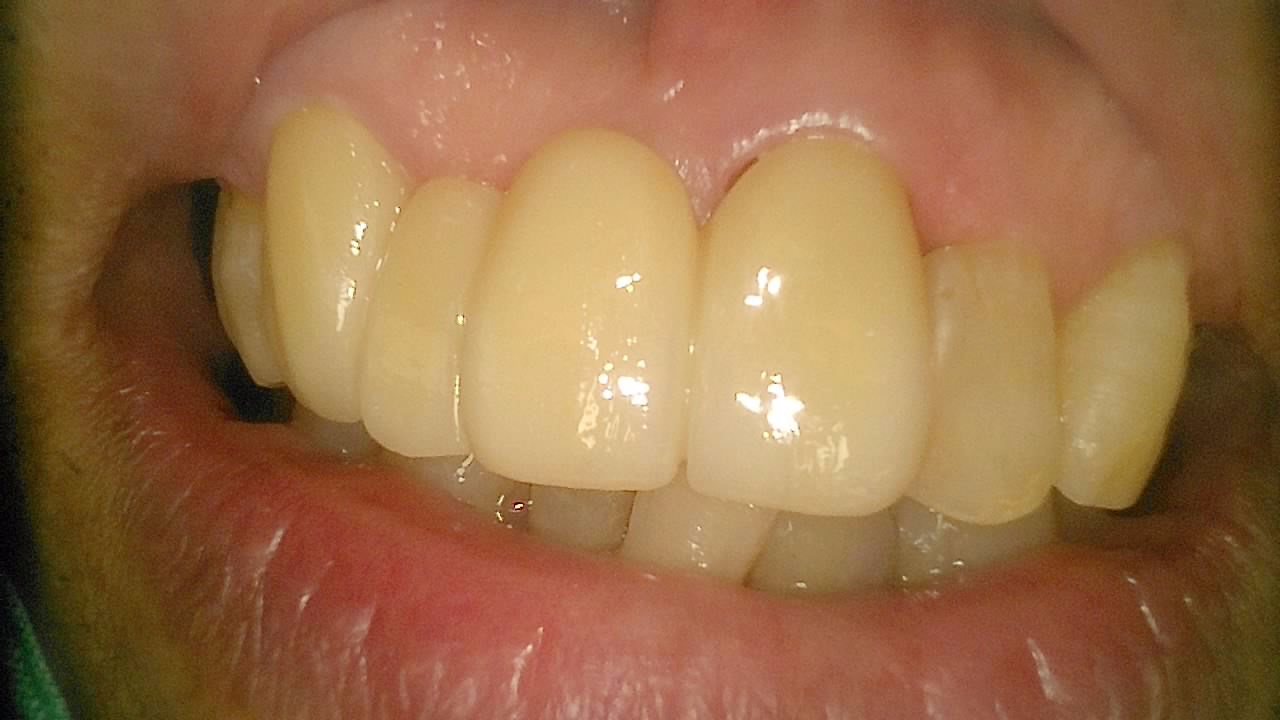

임플란트

BEFORE & AFTER

일반진료